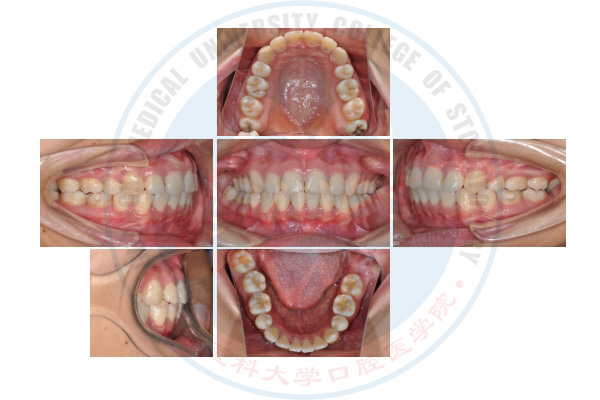

微种植体支抗技术

正畸治疗前

正畸治疗中

正畸治疗后

正畸前后侧貌改变